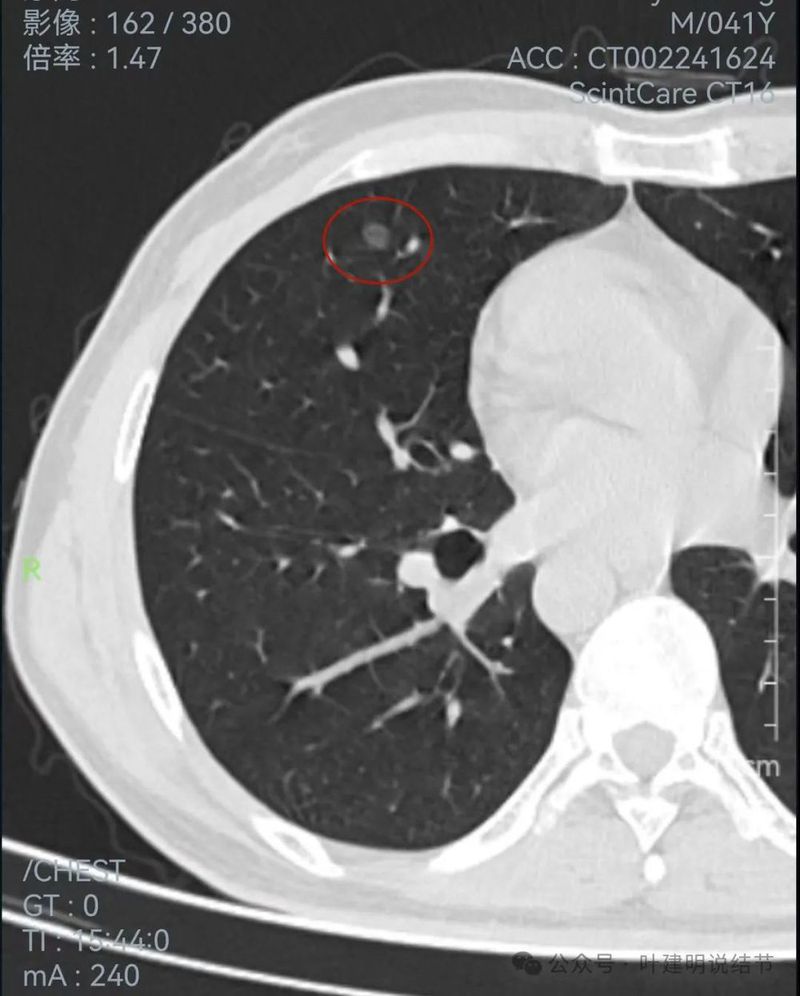

右侧病灶连续层面:

病灶出现,密度较淡。

轮廓清楚,血管贴边,也有血管弯征,瘤肺边界清楚。

轮廓与边界清,没有明显实性成分。

中间的密度稍低于周围部位。

轮廓清楚,边缘不光滑。

边缘区较淡。